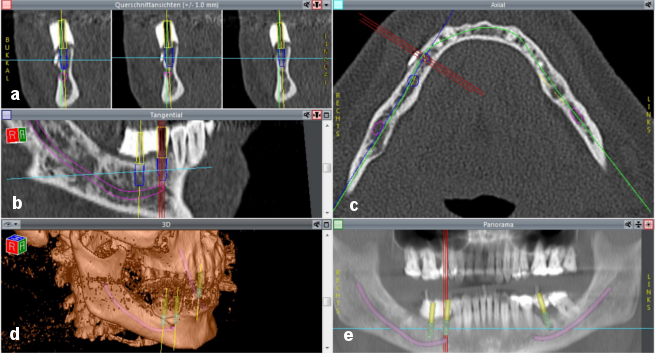

Implant planning and simulation were performed with CoDiagnostiX software (version 6.0, IVS Solutions AG, Chemnitz, Germany). CT data (in DICOM format) were imported into the software, which was then used to virtually place implants into their position and to assess them in multiplanar (axial, coronal and sagittal) and three-dimensional views. In addition, a pseudo-panoramic radiograph was created (Figure 6a-e [Fig. 6]).

Figure 6: Screenshot demonstrating implant planning a) coronal view; b) sagittal view; c) axial view; d) 3D view; e) pseudo-panoramic radiograph. The purple line demonstrates the inferior alveolar nerve. The blue cylinders represent the implants selected from the implant library. The yellow cylinders show the virtual abutments, which allow the implants to be placed in relation to the planned positions of the abutments. This allows an adequate prosthetic restoration to be achieved on the basis of the principle of backwards planning. Once the set-up was completed, the scan template was filled with barium sulfate. The planned location of the abutments was created in the template with a pilot drill. The green line (c) represents the panoramic curve, which allows a pseudo-panoramic radiograph to be generated. The yellow lines (a, b and d) show the vertical axis of the implant. The light blue lines show the horizontal axis of the implant. The three red lines (b, c and e) represent the axes of the implant that is being positioned.

In addition, an abutment can be freely defined and virtually assigned to an implant. Abutment diameter, height, inclination and rotation can be changed as required. A virtual abutment allows the ideal implant position to be determined depending on the requirements that the implant axes must meet for an appropriate prosthetic restoration. Using the backwards planning approach, it is thus possible to achieve an esthetically and functionally satisfying prosthetic restoration. The procedure benefits from the use of barium sulfate that is filled into the scan template once the set-up has been completed. A pilot drill is then used to create the planned location of the abutments in the template. Implants can thus be positioned accurately in three dimensions on the basis of the planned prosthetic restoration (Figure 6a,b,e [Fig. 6]).